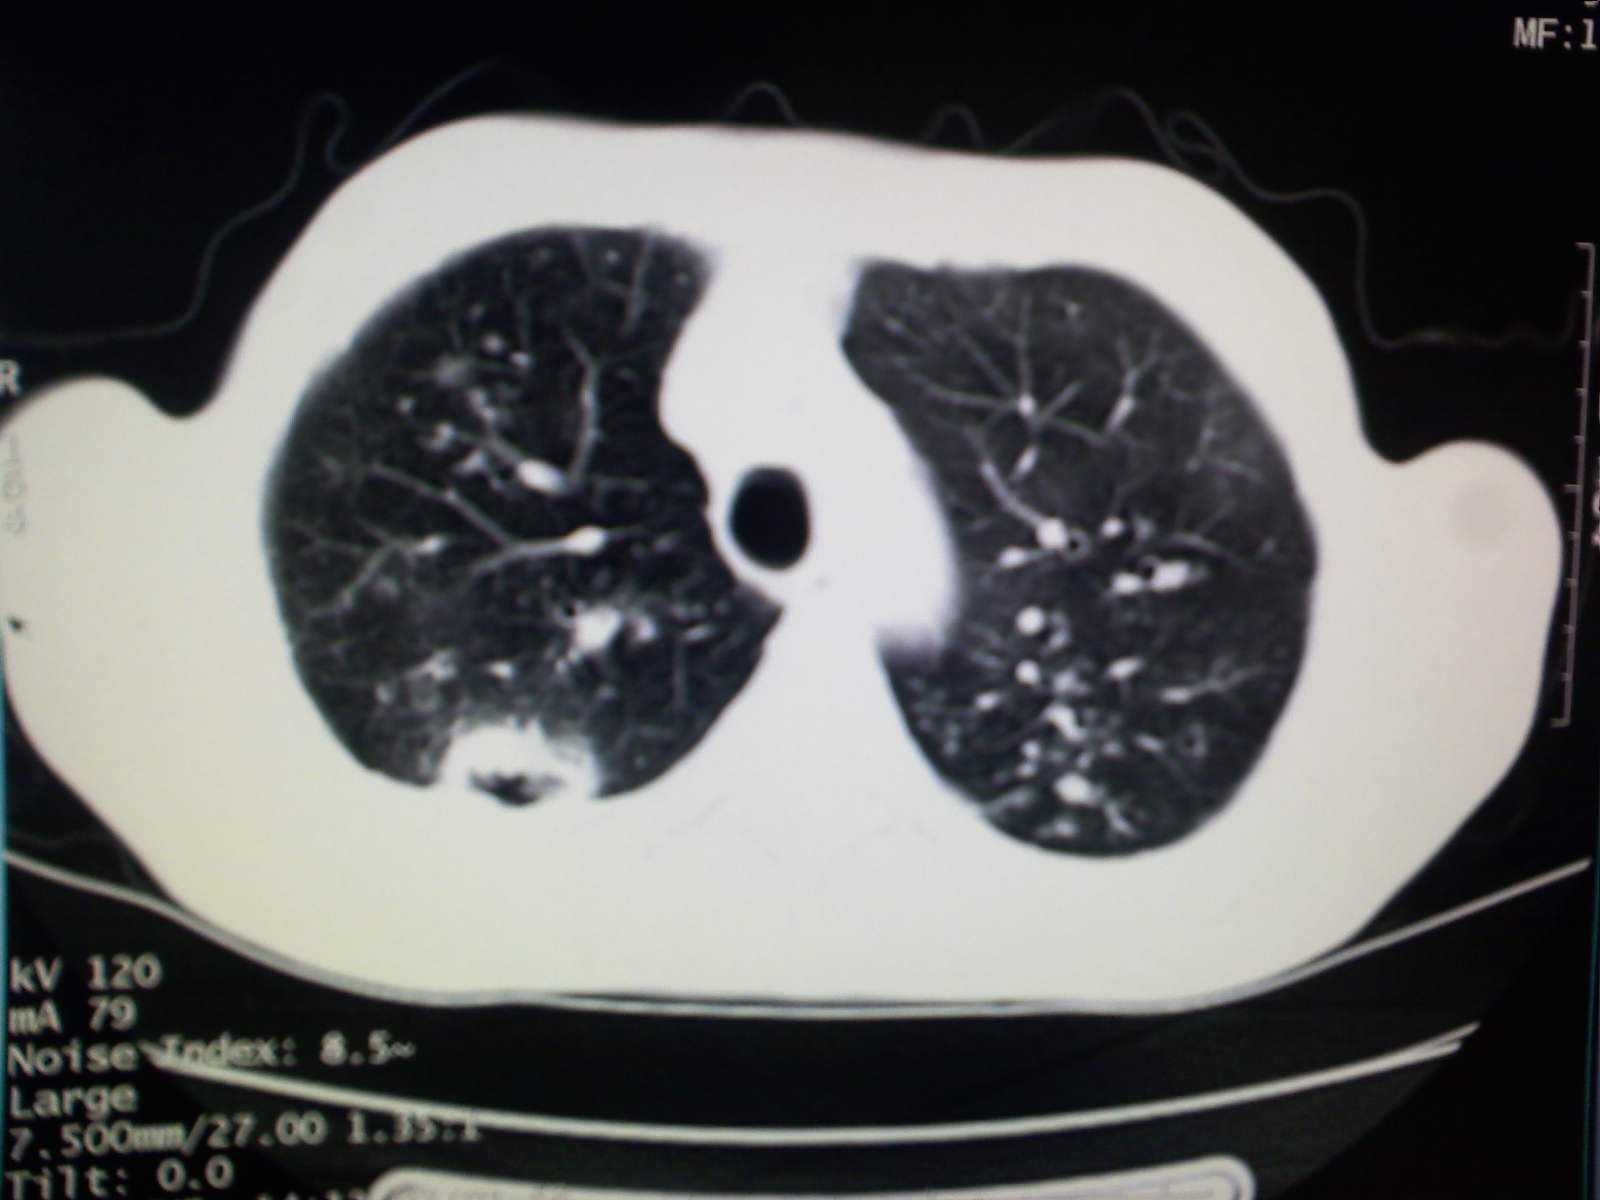

以下是引用卜一在2009-4-11 15:50:00的发言:[br]双肺继发性肺结核伴空洞形成,不排除合并霉菌感染!(病灶呈多形态 多特征 散在分布)。另:合并支气管扩张征伴感染!

以下是引用主力军在2009-4-11 15:55:00的发言:[br]两肺继发性肺结核可能性大。

以下是引用康鹏在2009-4-11 16:30:00的发言:[br]双肺继发性肺结核伴空洞形成合并感染[br]支气管扩张合并感染